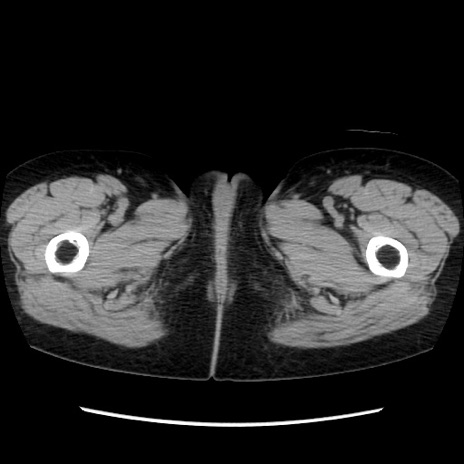

矢状断像

【症例】40歳代 女性

【主訴】上腹部痛、嘔気・嘔吐

【現病歴】約9時間前頃から急に上腹部痛、嘔気、嘔吐が出現。改善しないため救急要請。

【既往歴】子宮頚癌(広汎子宮全摘術、放射線療法)、腸閉塞

【身体所見】腹部:平坦、軟、腸雑音亢進、上腹部を中心に腹部全体に圧痛あり。

【データ】WBC 8400、CRP 0.03